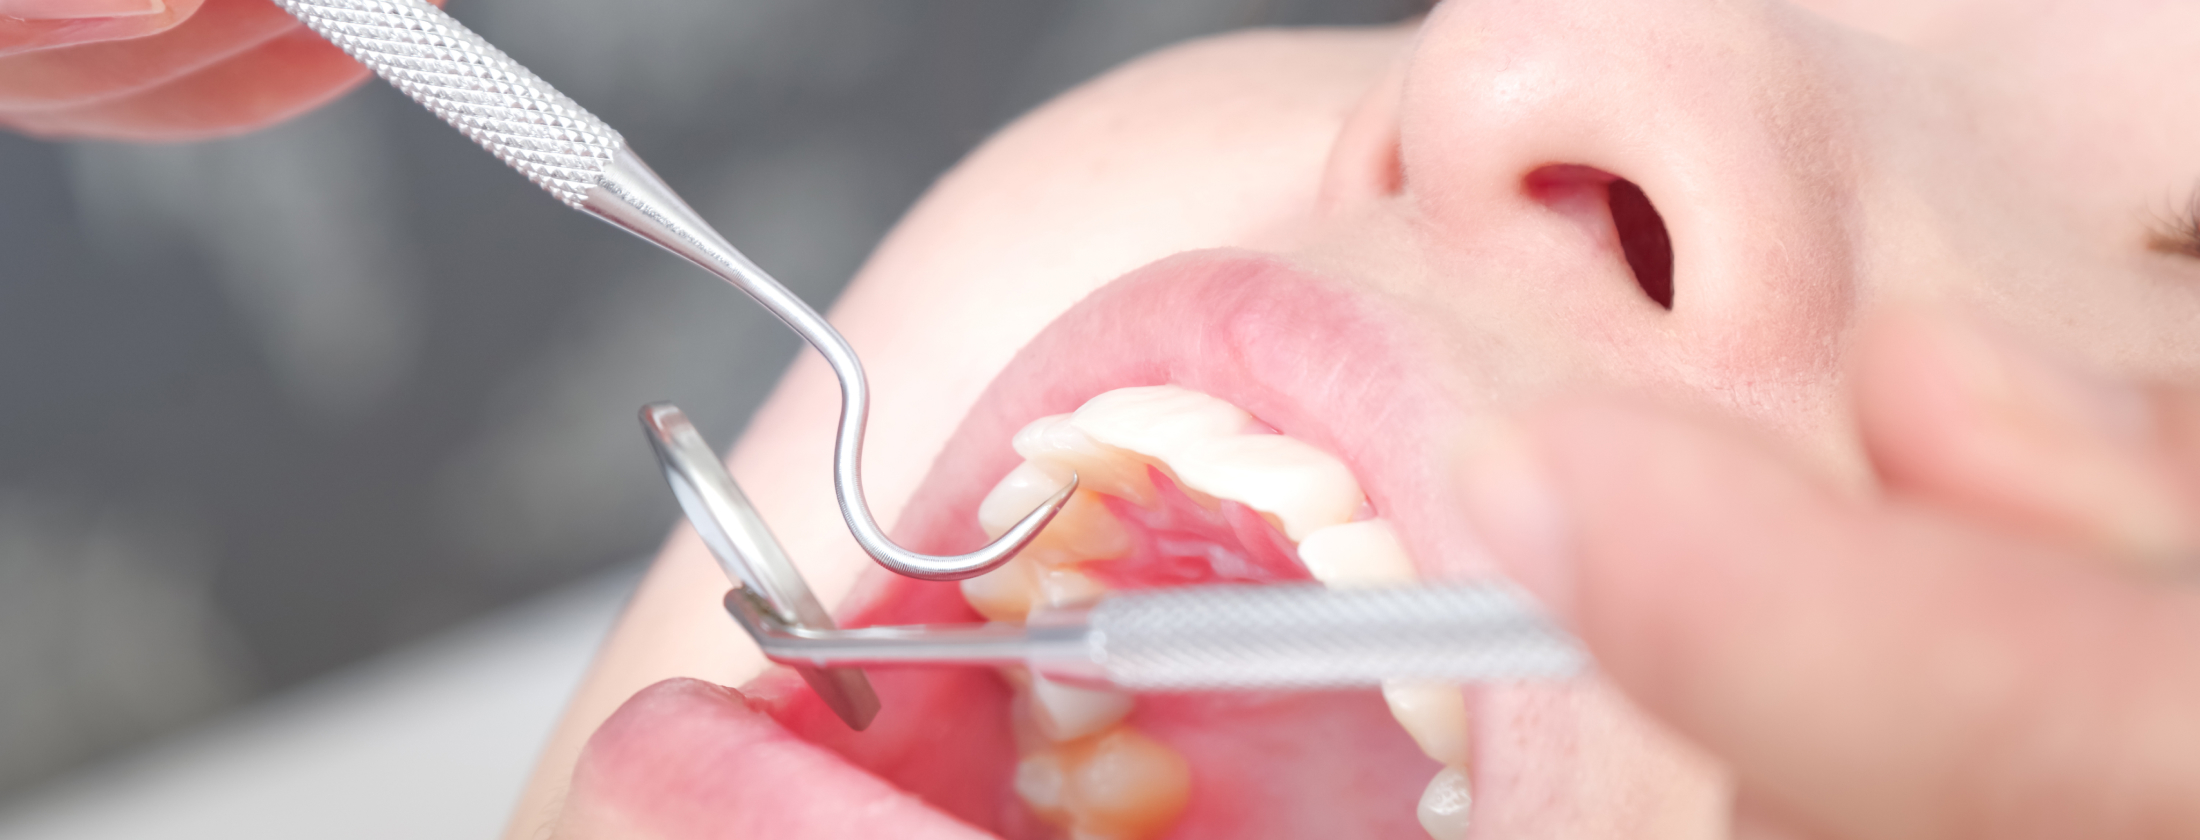

1.親知らずのトラブルは「早期対応」で未来が変わる

親知らずは、ただの“奥歯の1本”ではありません。

生え方や方向によっては、痛み・腫れ・虫歯・歯周病・噛み合わせの乱れなど、口腔環境全体に深刻な影響を与えることがあります。

“親知らずを抜く=怖い”を変えるために

多くの患者様が、「腫れそう」「痛そう」「怖い」「失敗しそう」と不安を抱えています。

LOTUS DENTAL CLINIC (ロータスデンタルクリニック)東京では、大学病院レベルの設備と外科体制を整え、難症例にも対応できる技術と経験を持つ医師が担当します。